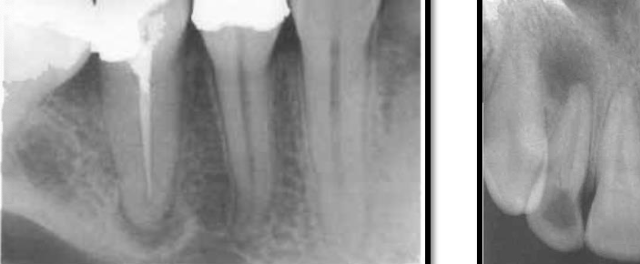

stage one – early cementoma

teeth remain vital

no treatment needed

appears as a radiolucent area

develops slowly over about 6 years

commonly found near:

MN incisors

stage two – mixed appearance

tooth is vital

typical around lower 1st molar region

shows a radiopaque area within the lesion

PDL space remains continuous around roots